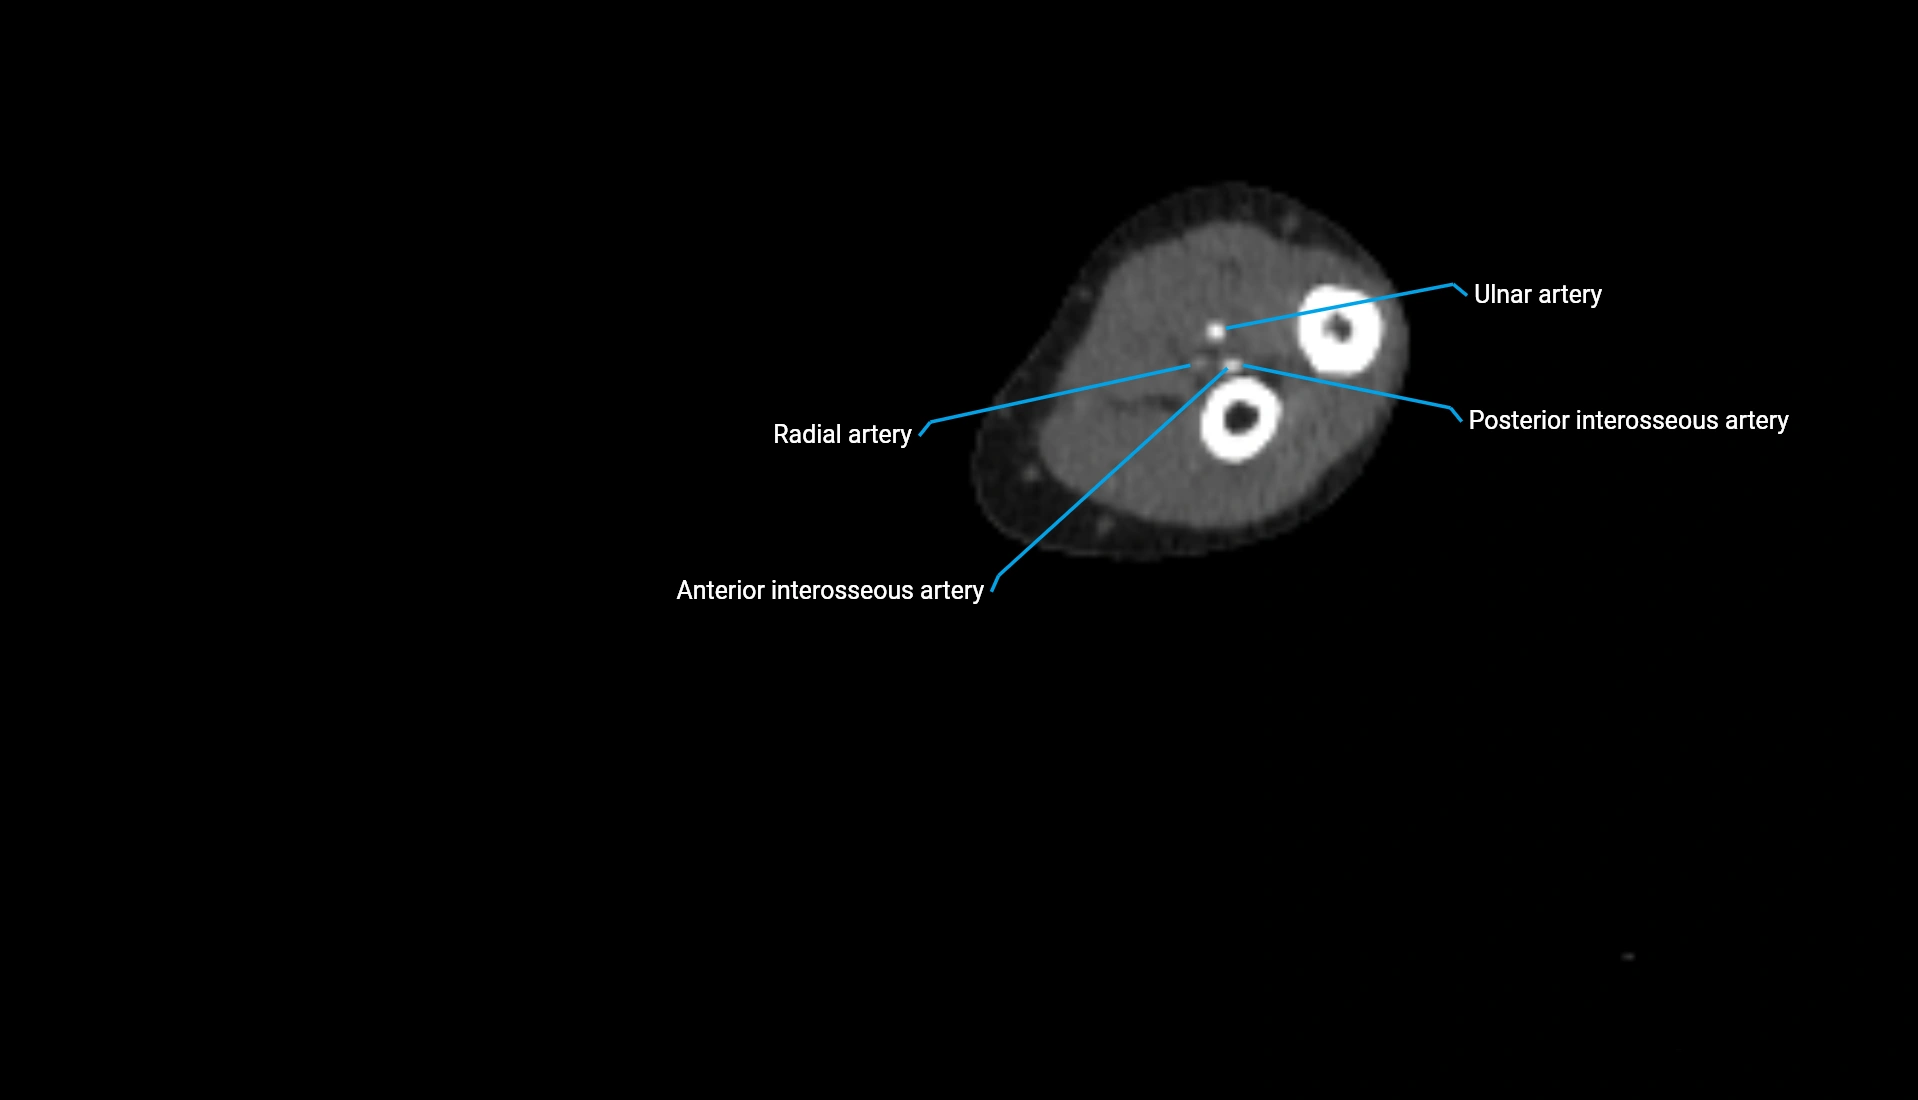

MRI image

image